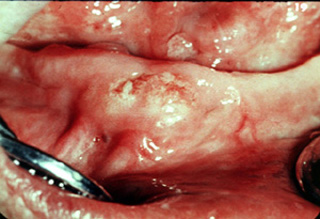

Manchado Esto es

una úlcera de carcinoma espinocelular de la mucosa bucal con apariencia

de "manchado". La combinación de rojo y blanco es muy significante y a menudo representa

una enfermedad maligna o "premaligna" . A primera vista

uno podría interpretar esta lesión como un trauma de la mucosa bucal

ocasionada por los dientes adyacentes. (Photograph courtesy of Dr. S. Rovin.) |